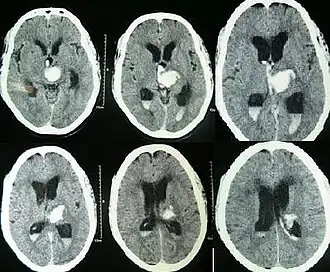

CT scan of a spontaneous intracerebral bleed, leaking into the lateral ventricles

Spontaneous ICH with hydrocephalus on CT scan[22]

Both computed tomography angiography (CTA) and magnetic resonance angiography (MRA) have been proved to be effective in diagnosing intracranial vascular malformations after ICH.[12] So frequently, a CT angiogram will be performed in order to exclude a secondary cause of hemorrhage[31] or to detect a "spot sign".

Intraparenchymal hemorrhage can be recognized on CT scans because blood appears brighter than other tissue and is separated from the inner table of the skull by brain tissue. The tissue surrounding a bleed is often less dense than the rest of the brain because of edema, and therefore shows up darker on the CT scan.[31] The oedema surrounding the haemorrhage would rapidly increase in size in the first 48 hours, and reached its maximum extent at day 14. The bigger the size of the haematoma, the larger its surrounding oedema.[32] Brain oedema formation is due to the breakdown of red blood cells, where haemoglobin and other contents of red blood cells are released. The release of these red blood cells contents causes toxic effect on the brain and causes brain oedema. Besides, the breaking down of blood-brain barrier also contributes to the odema formation.[13]